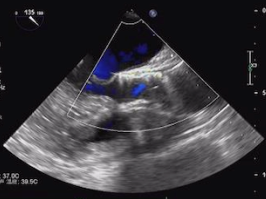

超声检查

• 左心房稍大;

• 升主动脉增宽;

• 室间隔与左室壁稍厚;

• 主动脉瓣重度狭窄并轻度反流;

• 二尖瓣轻微反流;

• 左室充盈功能减弱;

• 左心室舒张末期内径:42mm;

• 左心室收缩末期内径:23mm;

• 主动脉瓣口流苏峰值:412cm/s;

• 主动脉瓣跨瓣压差:60mmHg。